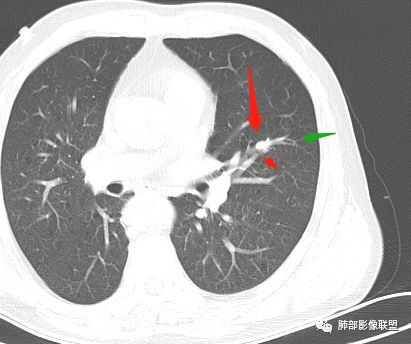

结节与下面的病灶有关系吗?

几个结节

下面这一支堵了

前后对比,这些结节其实是没引起支气管远端病变的

南大标注,这几个确实结节没有阻塞支气管,感觉是在血管分叉地方。

@南边 关键是上面这几个结节有的密度度,有的密度低。与下面堵塞支气管的结节样改变是否不是一回事,

如果下面堵塞是恶性,那上面的是不是考虑转移?另外一年结那个疑似结节的地方与现在堵塞的地方好象不一致。